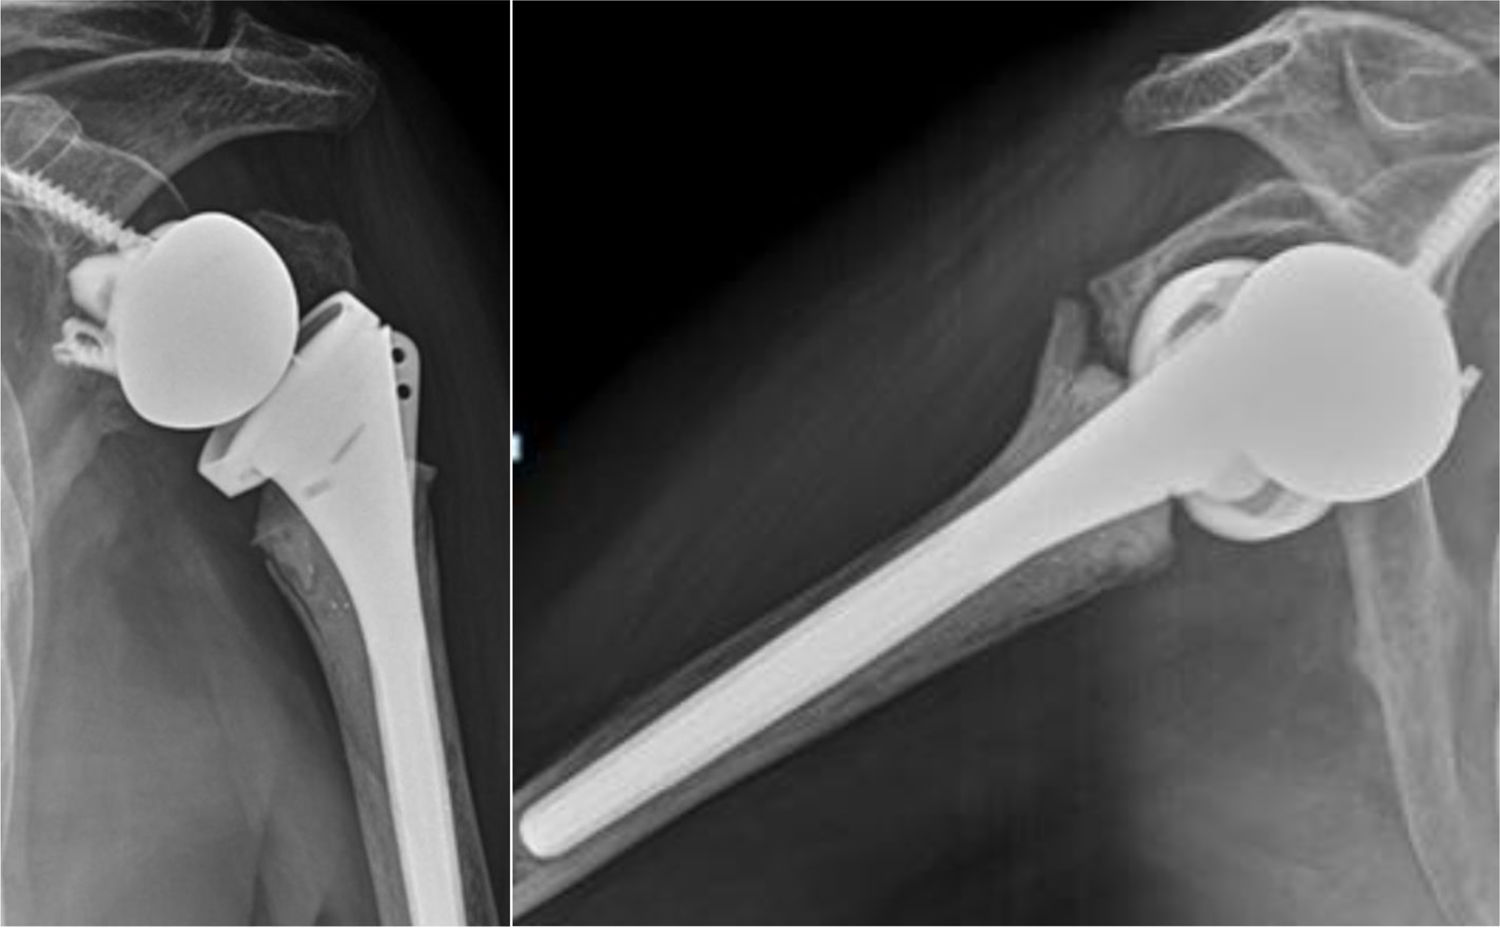

La consolidación anatómica se definió en la radiografía anteroposterior (AP) con rotación neutra, al observar la tuberosidad mayor a nivel de la cara lateral del vástago humeral, en contacto con la diáfisis y sin sobrepasar el extremo superior del polietileno (fig. 2). Se consideró consolidación no anatómica cuando la tuberosidad no era visible en la radiografía de hombro anteroposterior, pero su consolidación se evidenciaba en la radiografía de perfil o axial, indicando una migración o traslación posterosuperior (fig. 3). Finalmente, se determinó como falla de consolidación la presencia de signos radiográficos de seudoartrosis o lisis en la radiografía anteroposterior de hombro y axial de escápula (fig. 4).

ResultadosEn total, se incluyeron 73 pacientes a los que se les realizo una ARH por FHP, con una mayoría de mujeres y una edad media de 76años (rango 65-94). El seguimiento fue mayor en el grupo MAL que en el grupoL: 30,9±12,8 meses versus 17,9±3,4meses, respectivamente. No se observaron diferencias estadísticas significativas entre los grupos en cuanto a edad, sexo, lado afectado ni tipo de fractura (tabla 1). En el análisis radiográfico, la consolidación tuberositaria global se evidenció en 60 (82,2%) de los casos, mientras que 13 pacientes (17,8%) mostraron signos compatibles con fallo de consolidación. El grupoL mostró una tasa de consolidación total significativamente mayor (100%) frente al grupo MAL (75,5%). El grupoL mostró una mayor proporción de consolidación anatómica, mientras que las fallas de consolidación ocurrieron exclusivamente en el grupo MAL. La diferencia en la distribución de los patrones de consolidación entre ambos grupos fue estadísticamente significativa (p=0,020; tabla 2).

DiscusiónEn nuestra serie, el 55% de los pacientes tratados con prótesis lateralizadas (grupoL) lograron una consolidación anatómica de las tuberosidades, sin presentarse casos de falla de consolidación. En contraste, entre los pacientes que recibieron una prótesis muy altamente lateralizada (grupo MAL), la consolidación anatómica se observó solo en el 28% de los casos, mientras que el 24,5% presentó una falta completa de consolidación. Esta diferencia fue estadísticamente significativa (p=0,020) y sugiere que un mayor grado de lateralización podría tener un efecto adverso sobre el proceso de osteointegración de las tuberosidades, particularmente en el contexto de fracturas agudas del húmero proximal.